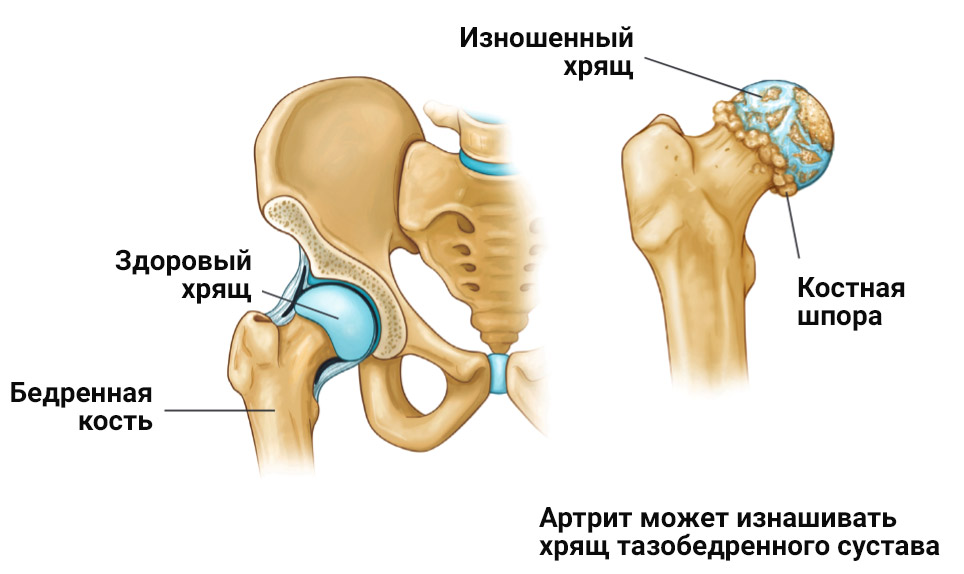

Остеоартрит фасеточных суставов: медицинские снимки и схемы